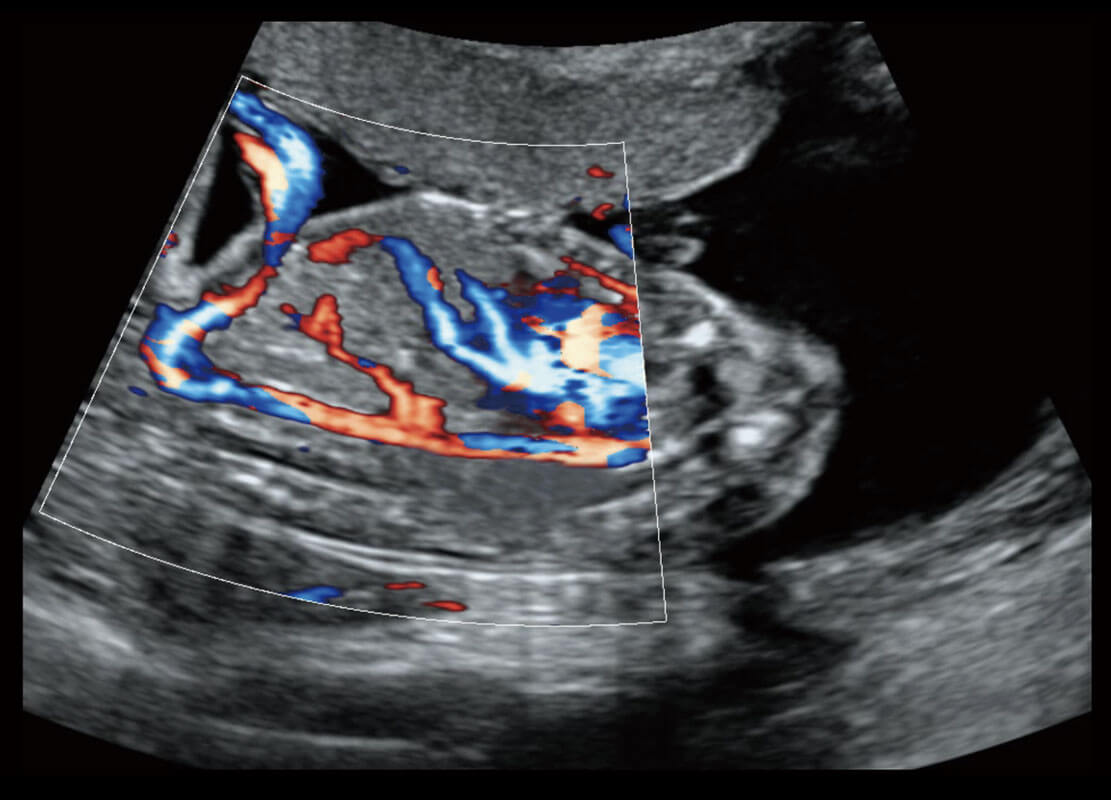

四腔心血流

P60搭载一系列胎儿心脏成像技术,实现精细的胎儿心脏评估。